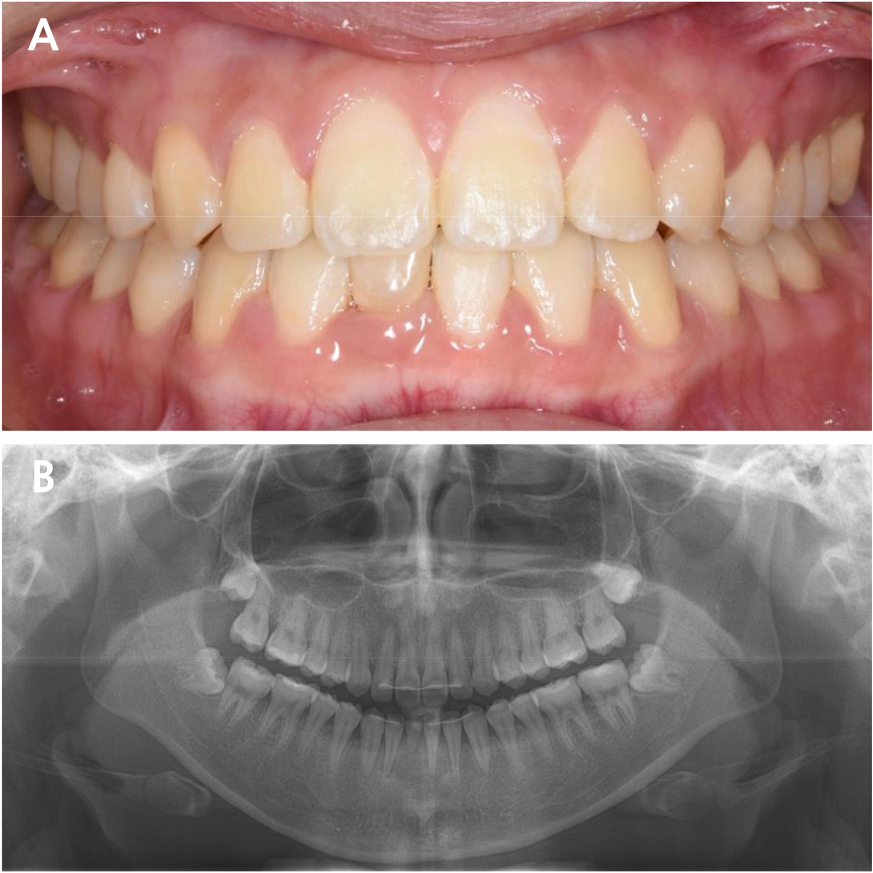

A 23-year-old woman was referred to the Department of Prosthodontics at the Dental Hospital of Seoul National University. The patient had recently completed orthodontic treatment, and a single prolonged retained primary mandibular right central incisor was scheduled for extraction. The patient had no relevant medical history. Intraoral examination revealed a prolonged retention of the primary mandibular right central incisor. The tooth showed a third-degree mobility. Severe root resorption of the retained tooth was visible on radiographic examination (Fig. 1).

Cone-beam computed tomography imaging was performed to evaluate bone width. The site of interest showed a narrow width, which is incapable of regular-diameter implants. Therefore, a one-piece mini-implant (MS Narrow Ridge; Osstem, Busan, Korea) with a diameter of 2.0 mm, length of 10 mm, and gingival height of 4 mm was planned for placement (Fig. 2). A computer-designed surgical guide was manufactured by an implant company (OneGuide; Osstem, Busan, Korea).